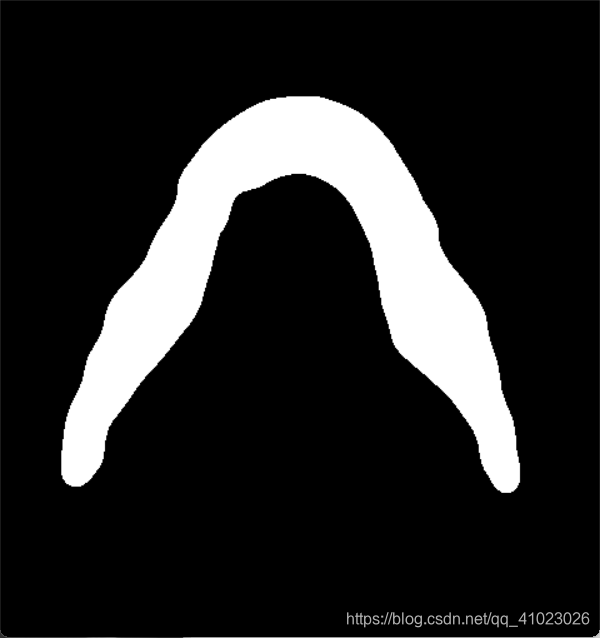

Mat srcMat5 = Mat::zeros(srcMat4.size(), CV_8UC1);

drawContours(srcMat5, contours, index, Scalar(255), FILLED);